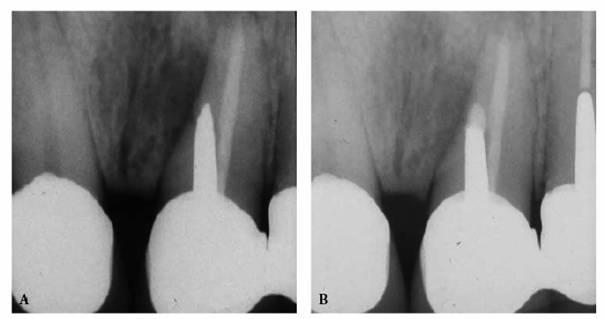

In most cases, an endodontic procedure should not be initiated without

evaluating at least two recent radiographs exposed at different horizontal

angulations of the suspected tooth (Figures 19-24A

and B).

Comparing varied views is essential in diagnosing the presence of additional

roots, anatomic configurations, anomalies, and other unusual circumstances that

may complicate the treatment.

Figure 19-24A and B: (A) Pretreatment radiograph of a mandibular premolar shows one canal. (B) A second radiograph taken from an angulation of 15 degrees from the mesial discloses a second root.